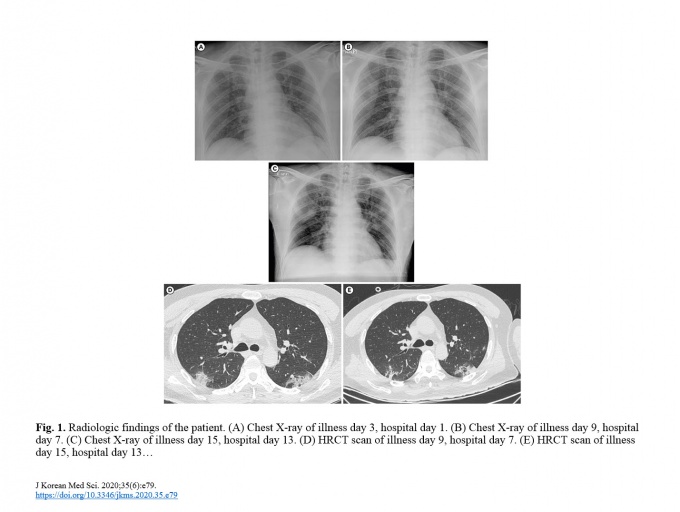

À̶§ ó¹æÇÑ Ä¡·áÁ¦´Â Ç×¹ÙÀÌ·¯½ºÁ¦ÀÎ Æä¶ó¹Ìºñ¸£(peramivir), Ç×»ýÁ¦ÀÎ ¼¼ÇÁÆ®¸®¾Ç¼Õ(ceftriaxone)ÀÌ´Ù. ÀÌÈÄ ÀÔ¿øÇÑ Áö 6Àϰ µÇ´Â ³¯ ÈäºÎCT¿¡¼­ Æó·Å Áõ»óÀÌ º¸¿´À¸¸ç Æó·Å Áø´Ü ÀÌÆ±³¯ºÎÅÍ Ä®·¹Æ®¶ó¸¦ ó¹æÇß´Ù.